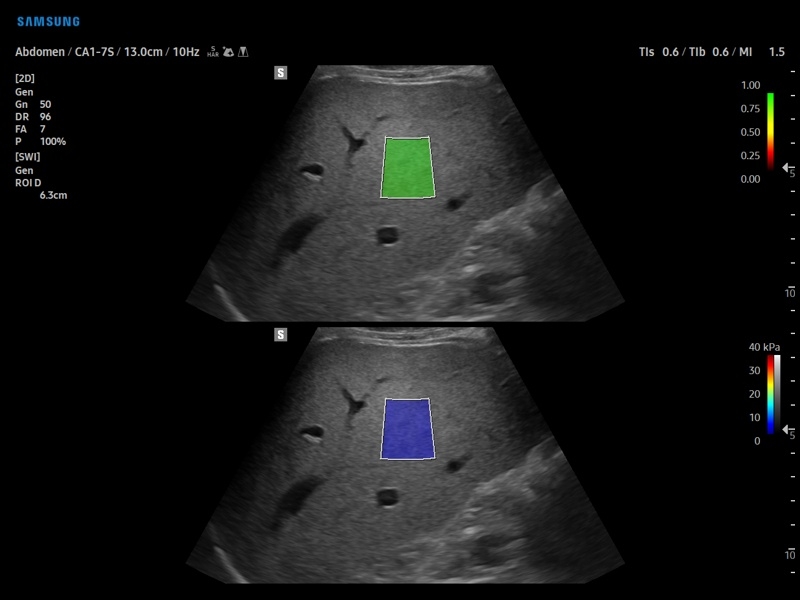

• S-Shearwave Imaging для эластографии сдвиговой волной

Компрессионная, Сдвиговая

Эластография сдвиговой волной/Эластометрия:

Да

• Модуль S-Shearwave imaging – программа цветовой сдвиговой эластографии позволяющая автоматически определять индекс жесткости различных участков исследуемого объекта в кПа или м/с, получая при это еще и индекс достоверности данных RMI.